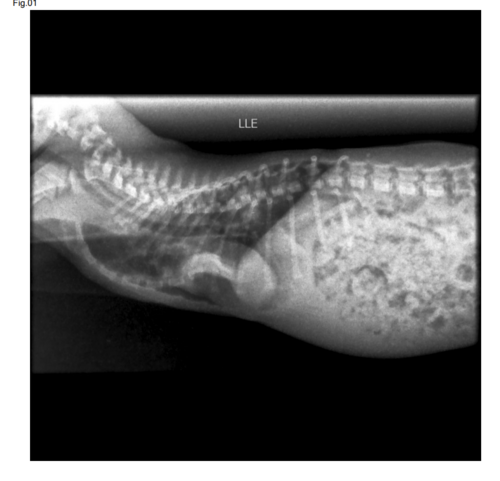

Meu nome é Bianca, estou criando essa vaquinha para poder inicialmente cobrir os exames do Jimin que tem apenas dois meses, e foi diagnosticado com uma doença rara chamada pectus excavatum. Preciso de ajuda com os custos dos exames e posteriormente com apoio para cirurgia, essa má formação congênita dificulta a respiração além do peito do animal ficar em formato de cone pressionando os órgãos do animal.Até o momento o quadro dele teve piora considerável e precisa de ajuda urgente com os exames para prosseguir com a cirurgia, qualquer valor ajuda.Segue imagens, e anexos do orçamento. Assim que tiver o custo da cirurgia compartilharei com vocês. Deus abençoe.